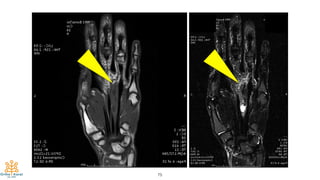

35-year-old, M

Painful mass at left

palm for 4 mo.

75

76

Intraoperative Finding:

Ill-defined intramuscular

mass of lumbrical muscle

with FDP, FDS tendon

involvement

Patho = Epithelioid Sarcoma

Margin: not free

Definitive Surgery:

“At least” Marginal resection

The 3rd & 4th ray amputation